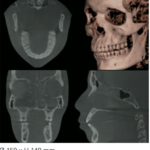

Macizo Facial

80 x 50 mm